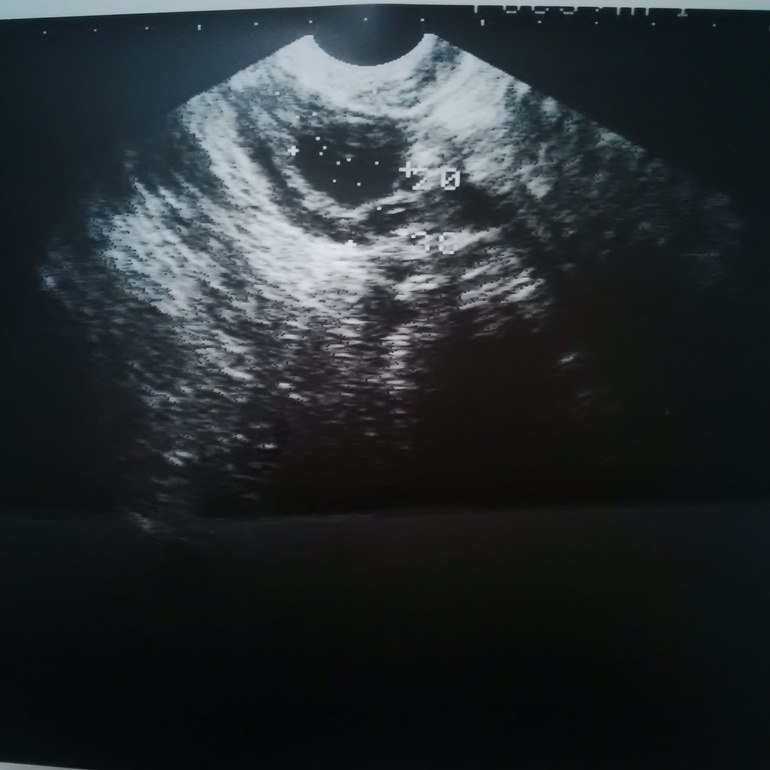

Киста или созревший фолликул?

ФолликулометрияДевочки, узистка молчит, к врачу еще нескоро. Это киста или фолликул 20 мм?

Так вот, это таки были 20 кист. Поликистоз. СПКЯ. Никакого желтого тела.

Похоже на желтое тело. А какой эндометрий по узи? Просто после О. он меняется.

ЖТ я думаю, вокруг капсула видна, у фолликула такого нет и границы четкие.

все ждала коментов чужих... Т.к я считаю что это ЖТ, но не хотела напутать вас. Вообщем походу я права и это жт, у фолликула контуры ровные и четкие, тут не ровные совершенно